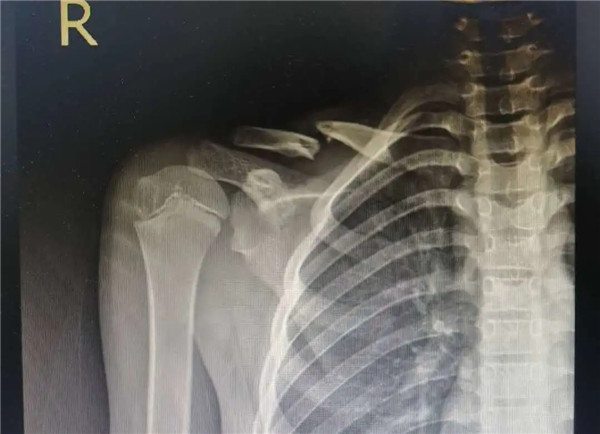

復(fù)位前

經(jīng)拍片顯示,洋洋右鎖骨中遠(yuǎn)段骨折。查體時(shí),洋洋右肩部腫脹,有壓痛感,右肩關(guān)節(jié)上舉、外展活動(dòng)受限,建議其入院并接受手術(shù)治療。洋洋媽媽當(dāng)即辦理了入院手續(xù)。